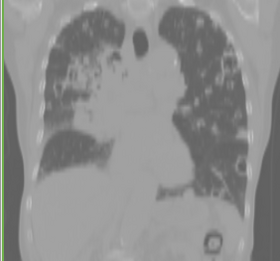

Plastimatch is an open source software for deformable image registration. It is designed for high-performance volumetric registration of medical images, such as X-ray computed tomography (CT), magnetic resonance imaging (MRI), and positron emission tomography (PET). Software features include:

- Intra-subject registration for adaptive radiotherapy

- Inter-subject registration for automatic segmentation